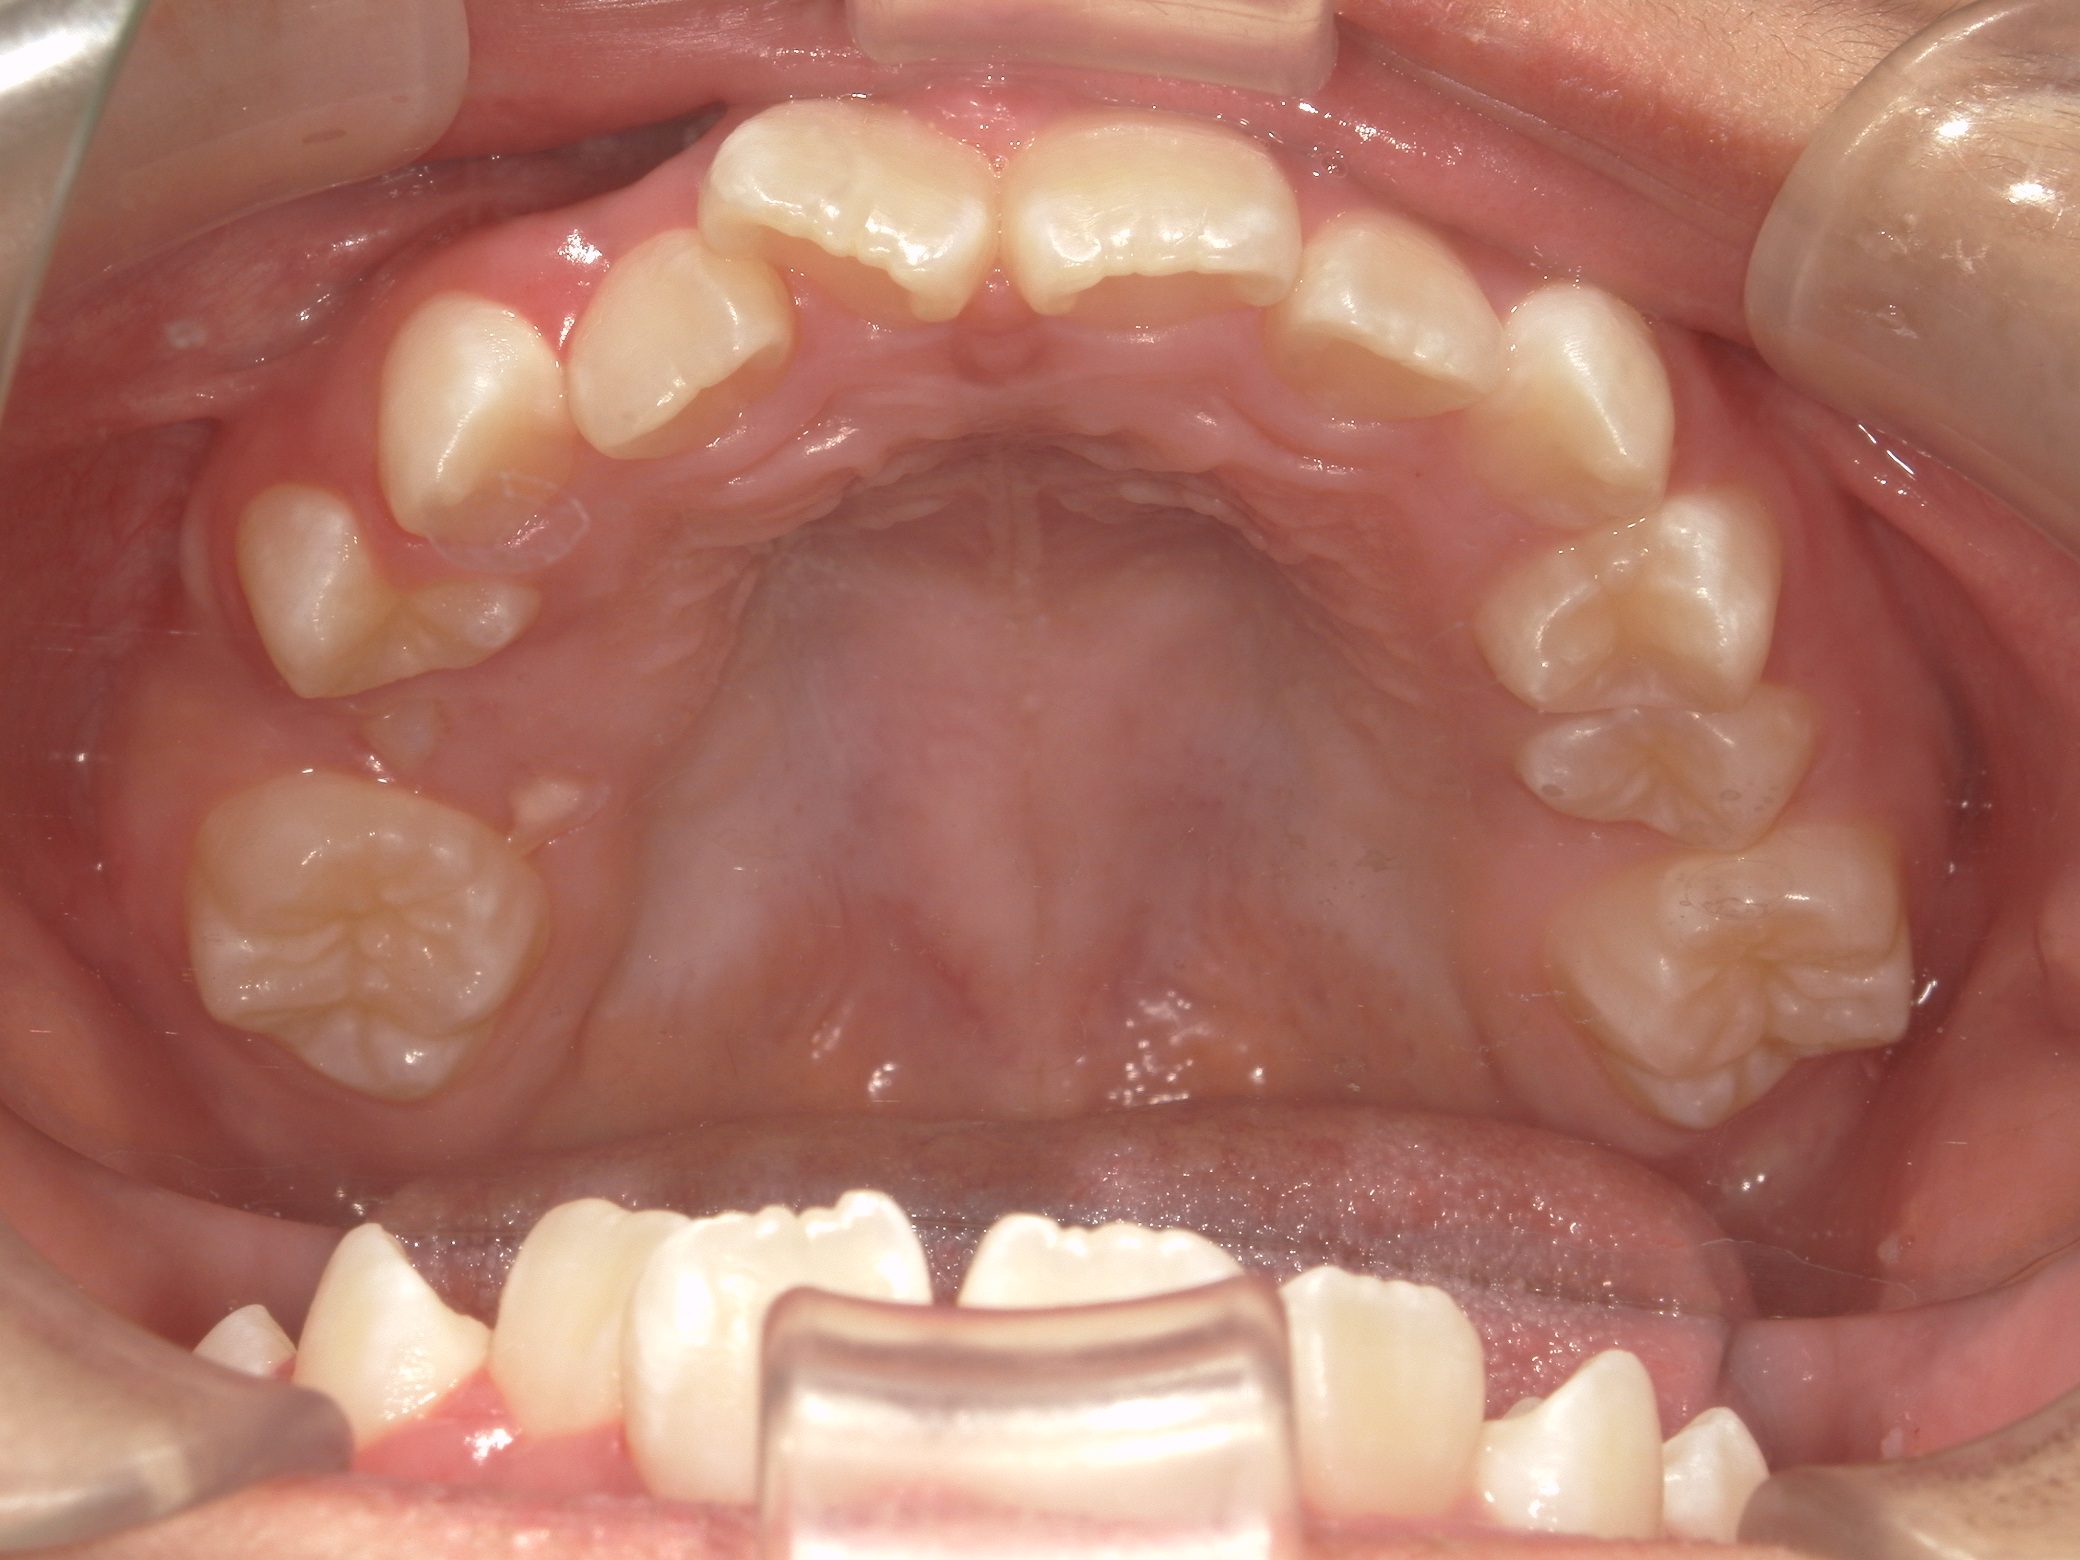

Before

After